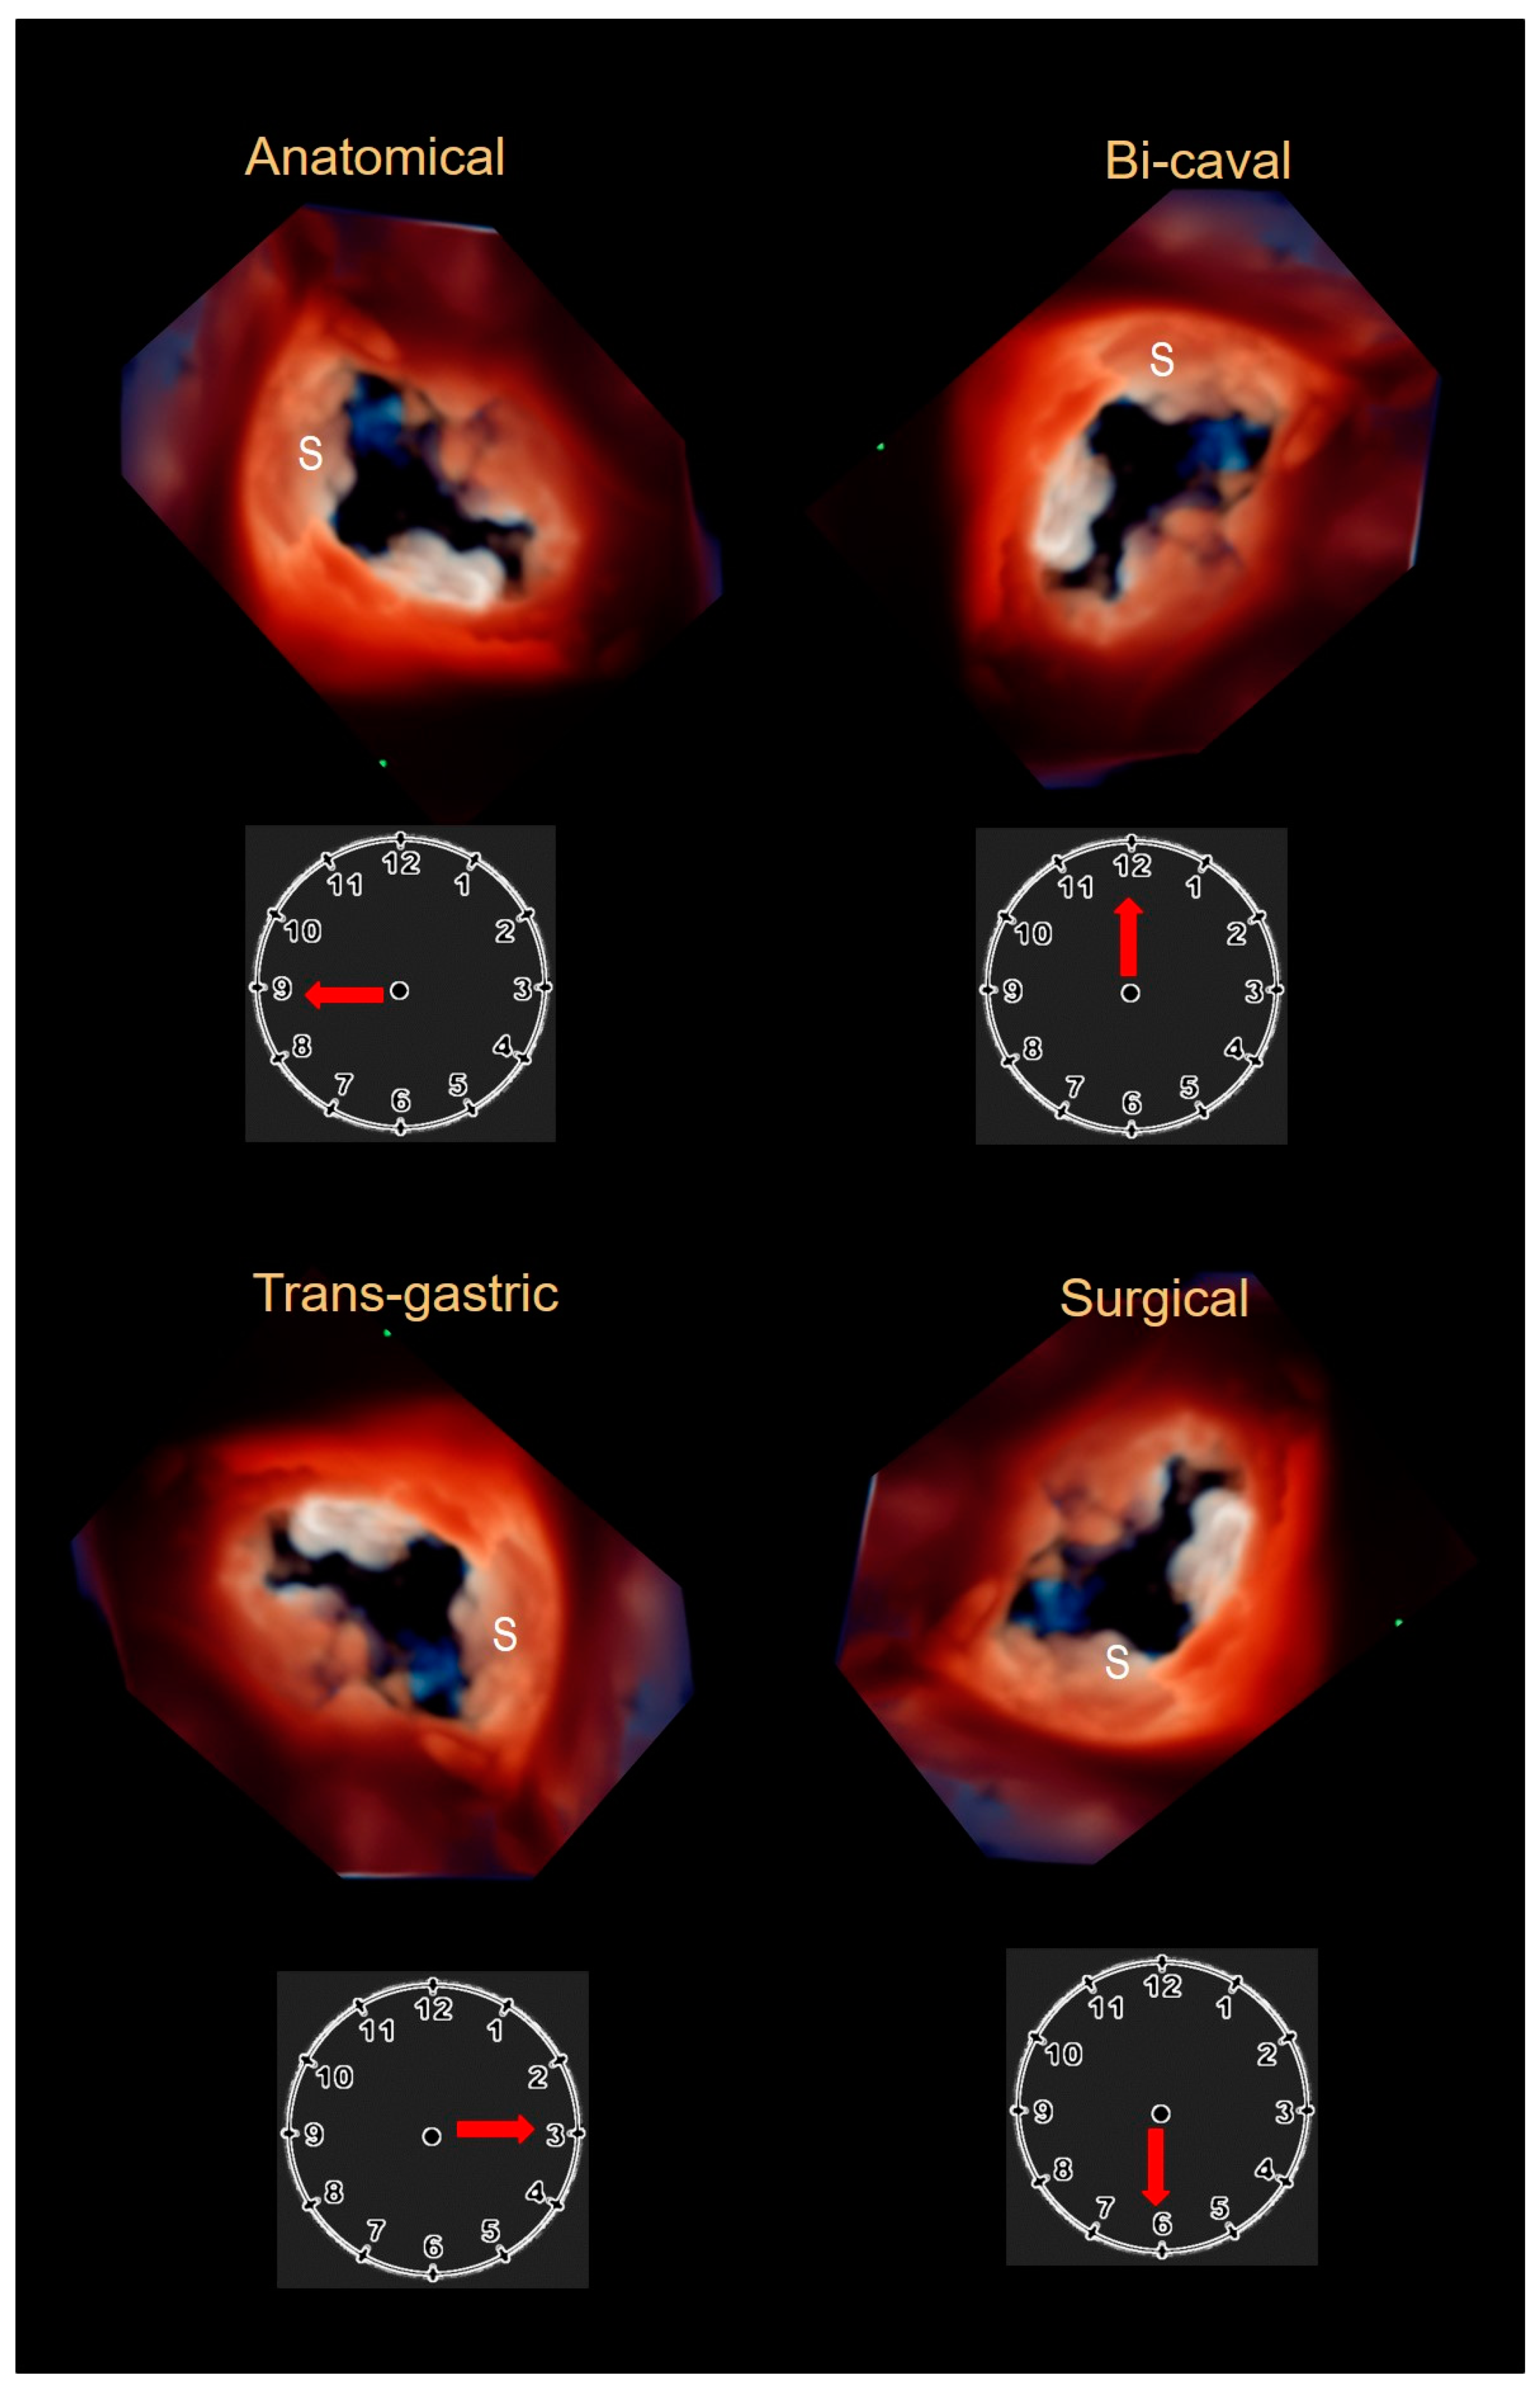

2.3. Echocardiography

- Hahn, R.T.; Nabauer, M.; Zuber, M.; Nazif, T.; Hausleiter, J.; Taramasso, M.; Pozzoli, A.; George, I.; Kodali, S.; Bapat, V.; et al. Intraprocedural Imaging of Transcatheter Tricuspid Valve Interventions. JACC Cardiovasc. Imaging 2019, 12, 532–553. [Google Scholar] [CrossRef] [PubMed]